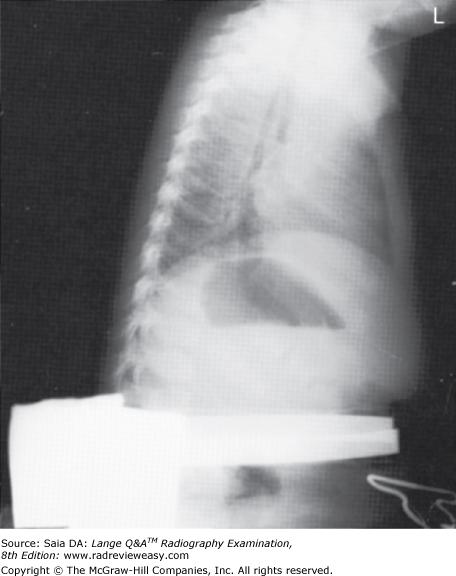

Which of the following statements is (are) true regarding the radiograph shown in Figure 6–16?

- The part is rotated.

- The patient is not shielded correctly.

- There is excessive receptor exposure.

A 1 only

B 2 only

C 1 and 2 only

D 1, 2, and 3

-The patient is well positioned; the spinous processes and sternum are seen clearly without superimposition. Adequate penetration and long-scale contrast are present without excessive receptor exposure. The patient had been shielded properly for the PA projection, but the shield was not moved to the correct location prior to the lateral exposure.